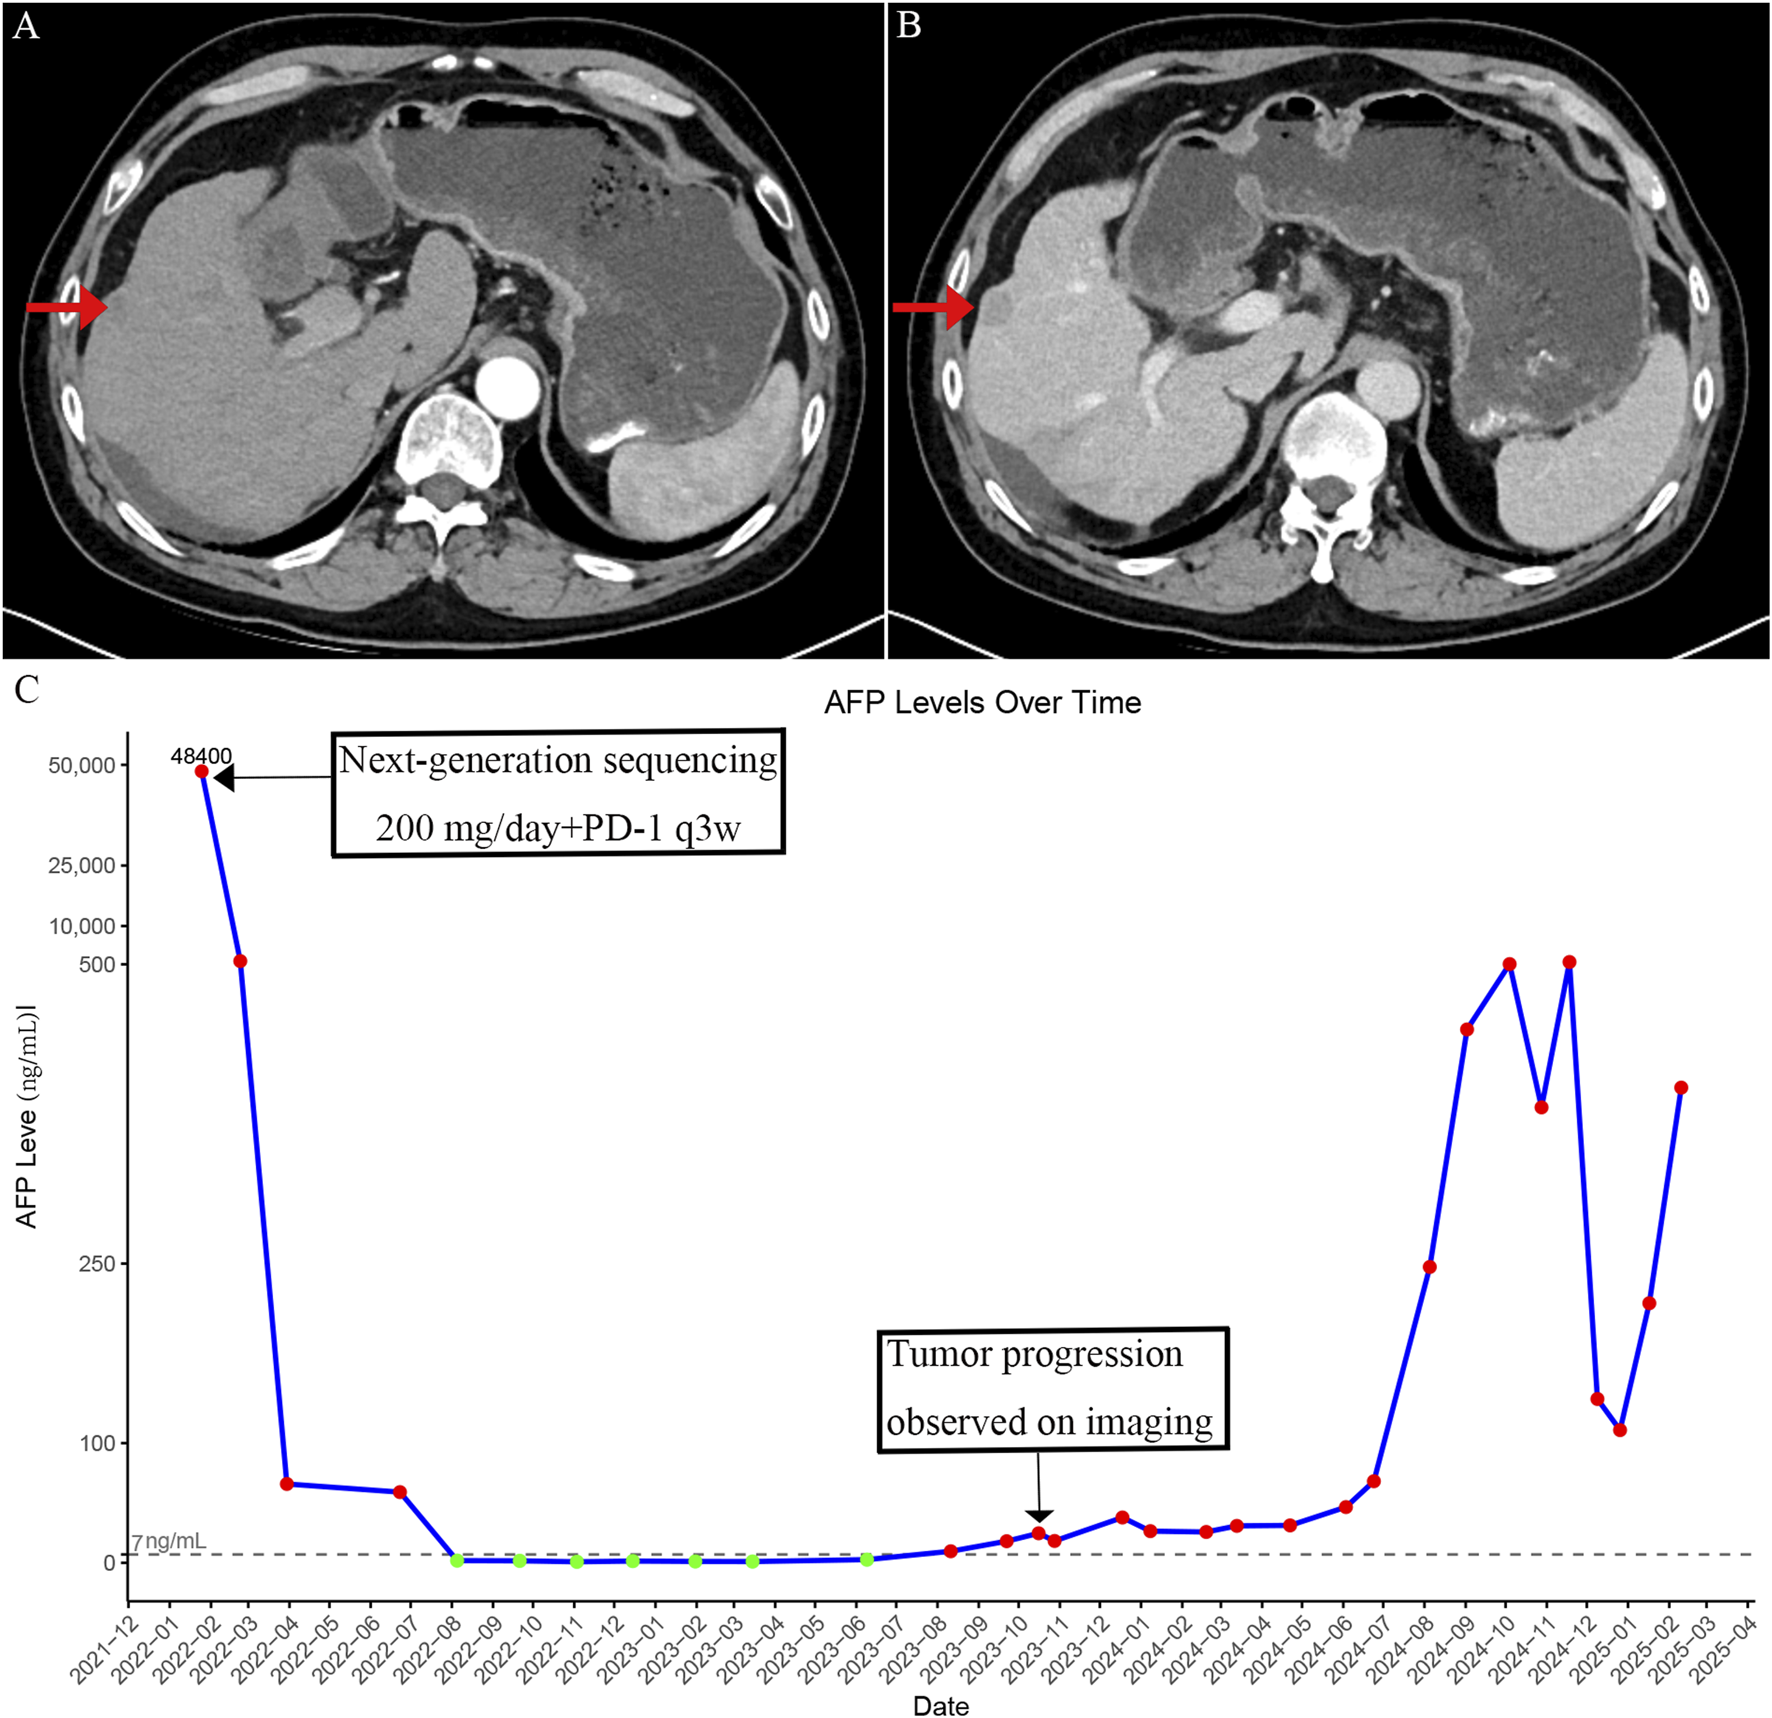

FIGURE 3

Imaging findings and serum alpha-fetoprotein (AFP) changes after development of resistance to crizotinib. (A) Arterial phase contrast-enhanced CT image showing intrahepatic recurrent nodules after acquired resistance to crizotinib. (B) Portal venous phase image showing decreased enhancement compared to the arterial phase in the recurrent intrahepatic lesions. (C) Time-course of serum AFP levels showing an initial decrease following crizotinib treatment, followed by a rise corresponding to disease progression after acquired resistance.

Unfortunately, after approximately 18 months of disease stability, a gradual and sustained increase in AFP was observed, eventually exceeding the normal range by August 2023 (Figure 3C). Imaging confirmed the emergence of new intrahepatic lesions (Figures 3A,B). In February 2025, a biopsy of the new hepatic lesion was performed, and NGS was repeated. However, no actionable mutations were identified (Table 2). Literature review suggests that resistance to MET-TKIs may be associated with specific mutations. MET-TKIs are classified into type I and type II inhibitors based on their binding modes to the ATP-binding pocket. It has been reported that mutations such as MET Y1230H confer resistance to type I MET-TKIs—including crizotinib, capmatinib, and tepotinib—but retain sensitivity to type II MET-TKIs, such as glesatinib and cabozantinib (Engstrom et al., 2017). Switching from a type I to a type II MET-TKI has been proposed as a strategy to overcome acquired resistance, especially in non-small cell lung cancer (NSCLC) (Cai et al., 2021). Despite the theoretical benefit, the patient was unable to afford cabozantinib due to its high cost and declined this treatment option. Subsequent treatments—including additional sessions of TACE and RFA, as well as changes in systemic therapies—yielded only temporary reductions in AFP levels, which quickly rebounded (Figure 3C). As of the latest follow-up, the patient remains alive but with persistent and uncontrolled disease activity. The most recent AFP level measured was 568 ng/mL.